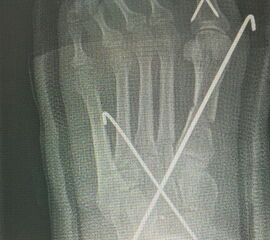

Werden komplette Osteotomien an den Zehen durchgeführt, fädeln wir die Osteotomien mit einem 1.2 oder 1.4 mm Kirschner-Draht auf, damit die einzelnen Fragmente nicht verkippen (Abb. 22).

Abb. 22 a-d: Präoperative Klauenzehen beim Jugendlichen in zwei Ansichten (a-b) und postoperative Auffädelung mit Kirschner-Drähten linker und rechter Fuß (c-d).

Nach unserer Erfahrung können komplette Osteotomien nicht so gut in einem Tapeverband stabil gehalten werden. Im Fall von Derotationen kombinieren wir einen Draht mit externen Tapezügeln, um das Ergebnis zu sichern. Die Drähte werden 2-3 Wochen belassen und anschließend in der Sprechstunde gezogen. Anschließend wird die Zehe noch 2 weitere Wochen mit Tape gezügelt (Abb. 23).